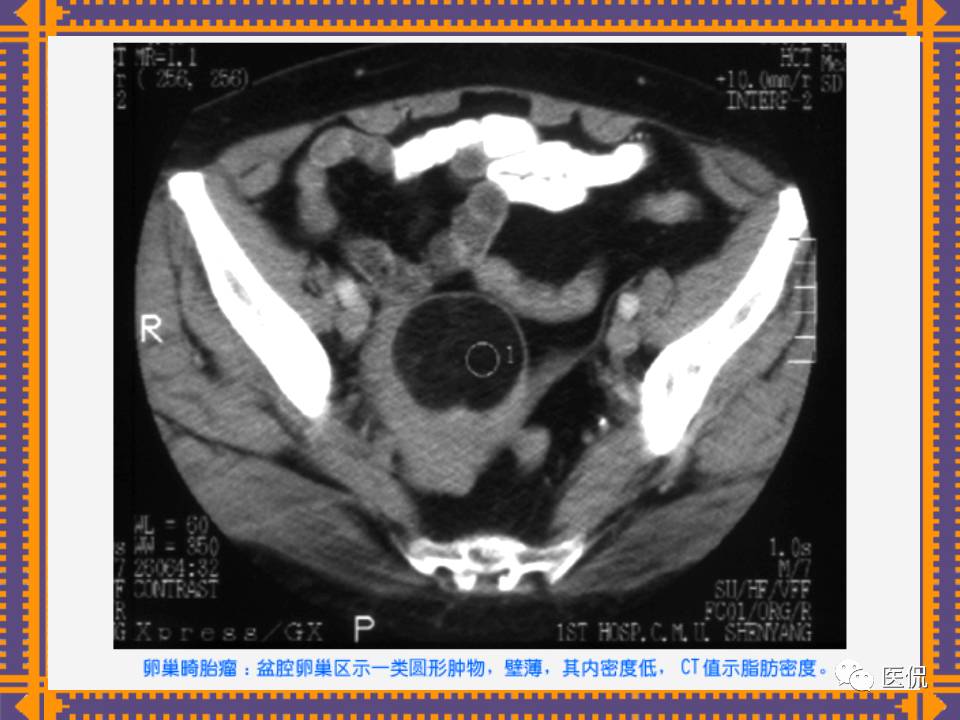

这篇PPT对男性生殖系统疾病:前列腺增生、前列腺癌;女性生殖系统疾病:子宫肌瘤、子宫癌、卵巢囊肿和卵巢肿瘤以及腹膜后间隙疾病进行了详细讲解。